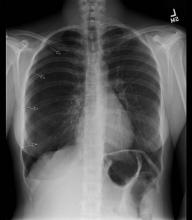

As with any procedure, informed consent is obtained and time-out conducted, including confirmation of identity and laterality with imaging studies (Figure 1 [3]). The site of insertion is the anterior chest wall, mid-clavicular line at the second intercostal space. A routine prep and drape is conducted (Figure 2 [4]). Next, local anesthetic (1% lidocaine) is infiltrated into the anterior 2nd intercostal space, staying just on the superior aspect of the rib. Typically, the authors have done this with local anesthetic (with minimal to no intravenous narcotics), and it is well tolerated (Figure 3 [5]). Once local anesthetic has been infiltrated, the introducer needle and catheter are used to aspirate air as the needle and catheter are advanced into pleural cavity (Figure 4 [6]). Once in the pleural cavity, a flexible guidewire is advanced into the pleural space (Figure 5 [7]). A small skin incision with a #11 scalpel facilitates passage of the dilator and subsequently the drain (Figure 6 [8]). The dilator is slowly advanced over the guidewire just enough to enter the pleural cavity. It is important to always maintain control of the end of the guidewire (Figure 7 [9]). Following dilation, the dilator is removed, and the percutaneous drain is advanced over the guidewire until the holes are all in the pleural cavity (Figure 8 [10]). Once the catheter is in the pleural cavity, tension on the drawstring locks the pigtail catheter. Finally, the pigtail catheter is connected to a Pneumostat valve or other water seal/collection device (Figures 9 [11] & 10 [12]).